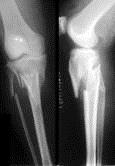

问题 病历摘要: 患者×××,男性,65岁,因车祸致伤左小腿后肿胀、活动受限、疼痛2小时。查体:左小腿上端肿胀,触痛(+),触及在骨擦音,左足伸足母、伸趾功能正常,足背动脉搏动正常。 关于骨不连的X线征,以下叙述哪些是正确的?

选项 A、假关节形成 B、骨质疏松 C、骨痂间无骨小梁形成 D、骨折端硬化,骨折面光滑清晰 E、骨髓腔封闭 F、骨折端有间隙

答案 ABCDEF

解析 ABCDEF